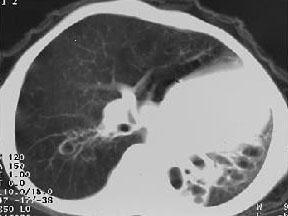

问题 女,8岁,如图所示,最可能诊断为 ( )

选项 A.左下肺不张 B.左下肺隔离症 C.左肺发育不全 D.左下肺支气管扩张 E.左下肺支气管囊肿

答案 C